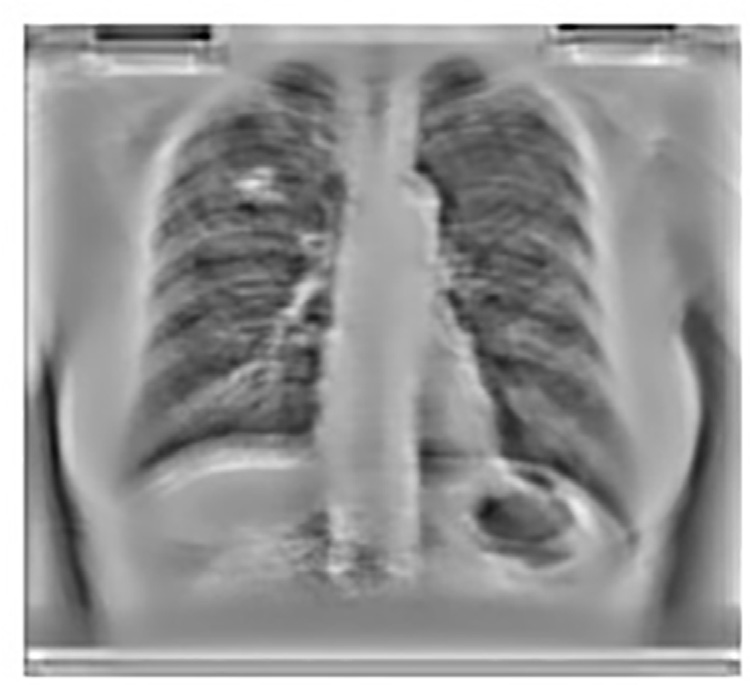

使用主成分分析滤波器进行肋骨抑制的结果如图14.2B所示。采用标准的高斯检测器高斯拉普拉斯掩模(LOG)来寻找可能存在结节的峰值区域。在原始胸部X光图像中应用该掩模导致了大量的假阳性,如图14.2A 所示,其中许多假阳性出现在肋骨上。

重复间隔估计为11个点长。因此,一个直接的解决方案是应用一个系数预先确定且固定的11点滑动平均FIR滤波器,其处理方式类似,并将结果M(x)用虚线绘制在同一张图上(图14.3)。可以看出,输出M(x)是平滑化版本,肋骨信号被抑制。这种平滑性是由于信号中对应于图像中肋骨边缘的高频成分被相对衰减所致。然而,为了对11点平均滤波器进行视觉评估,该滤波器被应用于图像的所有列上。结果如图14.5所示,其中明显看出,FIR滤波器模糊了胸部图像中存在的软组织,实际上可能模糊潜在结节的形状。如果将此图像输入结节检测机制,会导致检测到的结节具有更大的半径。因此可以安全地认为,固定线性滤波不适合在保留其余数据完整性的同时抑制肋骨。

应用PCA滤波后获得的图像如图14.8 所示,该图显示与使用均值滤波器提取的结果(如图14.5所示)相比,软组织受损更少。